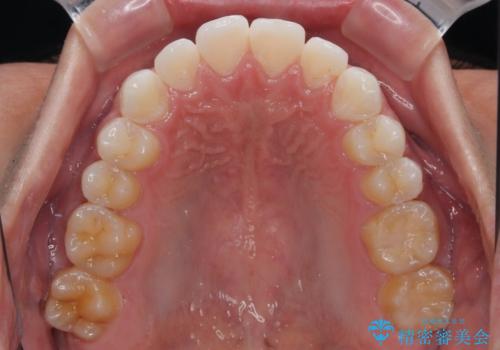

矯正治療後は、奥歯の銀歯をセラミッククラウンにて補綴治療を行うこととしました。

あっという間に歯列が整い、目立っていた銀歯もなくなり、清潔感のある口元になりました。